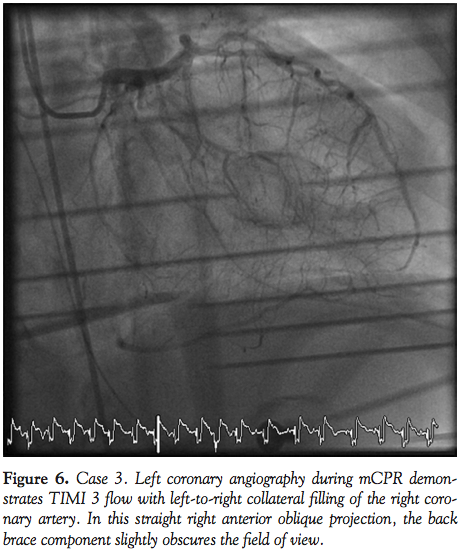

Case 3. A 66-year-old woman with a history of end-stage renal disease with failed cadaveric renal transplant, diabetes mellitus, and hypertension collapsed at home and EMS was activated. She suffered recurrent PEA cardiac arrest in the field and after arrival to the emergency department at a local hospital. After restoration of circulation, her ECG demonstrated an acute inferior STEMI and she was transferred to our facility for primary PCI. The patient suffered recurrent PEA upon arrival in the CCL and mCPR was initiated. Left coronary angiography was performed during mCPR showing collateral filling of the RCA up to its ostial segment (Figure 6). Her right coronary artery was occluded at the origin and could not be engaged with a guiding catheter despite multiple attempts. Because of recurrent episodes of PEA, long cumulative CPR duration, and a poor prognosis, no further attempts at RCA PCI were made. After additional vasopressors and mCPR, she regained spontaneous circulation and was transferred to the CCU. The patient’s requirement for vasopressor support increased and she expired 3 hours later.

Fluoroscopic and cineangiographic imaging during mCPR with the LUCAS device requires few significant adjustments. The images presented here represent one center’s experience and diagnostic images were obtained in all cases. Anterior-posterior projections are limited by the height and radio-opacity of the LUCAS drive unit over the patient’s chest. Straight right and left anterior oblique views provide adequate visualization despite the back-brace component of the device being visible on fluoroscopy. As evidenced in Cases 1 and 4, significant cranial angulation (>30°) can provide coronary imaging without visual encroachment by the device components.

In animal models, cerebral blood flow during CPR is improved with mCPR,15 and mCPR devices provide significantly higher coronary perfusion pressures than manual CPR.16 Coronary flow assessment has been reported in both animal models and human subjects.16,17 In 4 out of 6 patients studied by Larsen et al with TIMI 3 flow during mCPR, invasive measurements documented adequate coronary perfusion pressure gradients. In the present experience, coronary flow during mCPR is pulsatile, but classification by TIMI grade is readily apparent. In Cases 1, 4, and 5, the PCI procedure itself was performed during mCPR compressions (Figures 1, 2, 8, and 10).